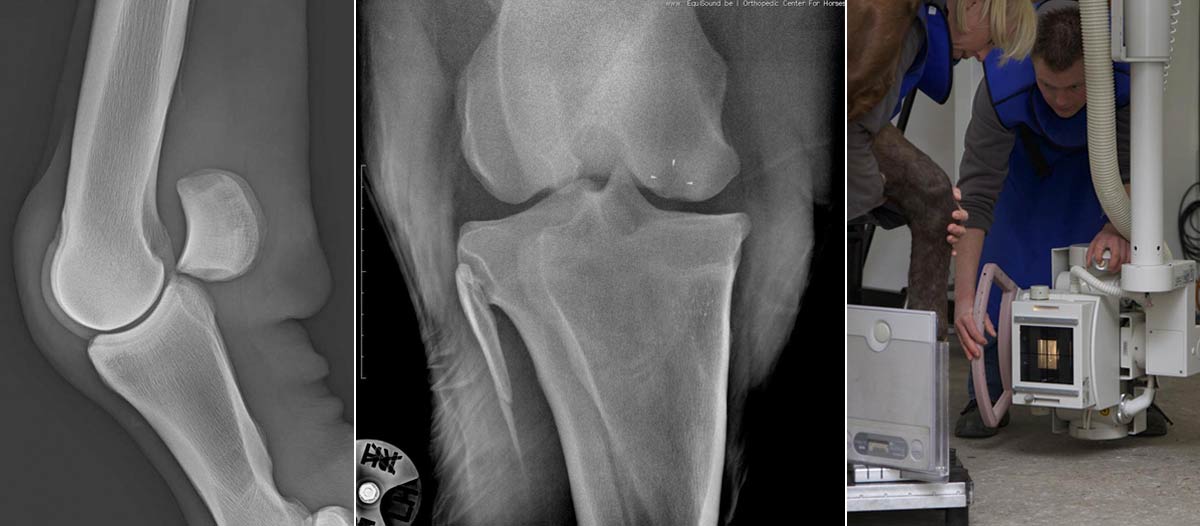

Radiographie

La radiographie est une technique ancienne qui connaît encore une grande évolution dans notre monde digital moderne. EquiSound dispose de 2 systèmes de radiographie digitale combinés à une machine à rayons X puissante de 80.000 Watts (80 kV). Nous pouvons produire des radiographies du cheval complet d’excellente qualité, tête, encolure et dos inclus.

Grâce à notre appareil radio portable et notre système DR, nous pouvons également offrir un service mobile et fournir des images de qualité chez vous lorsque votre cheval ne peut pas être transporté vers la clinique.